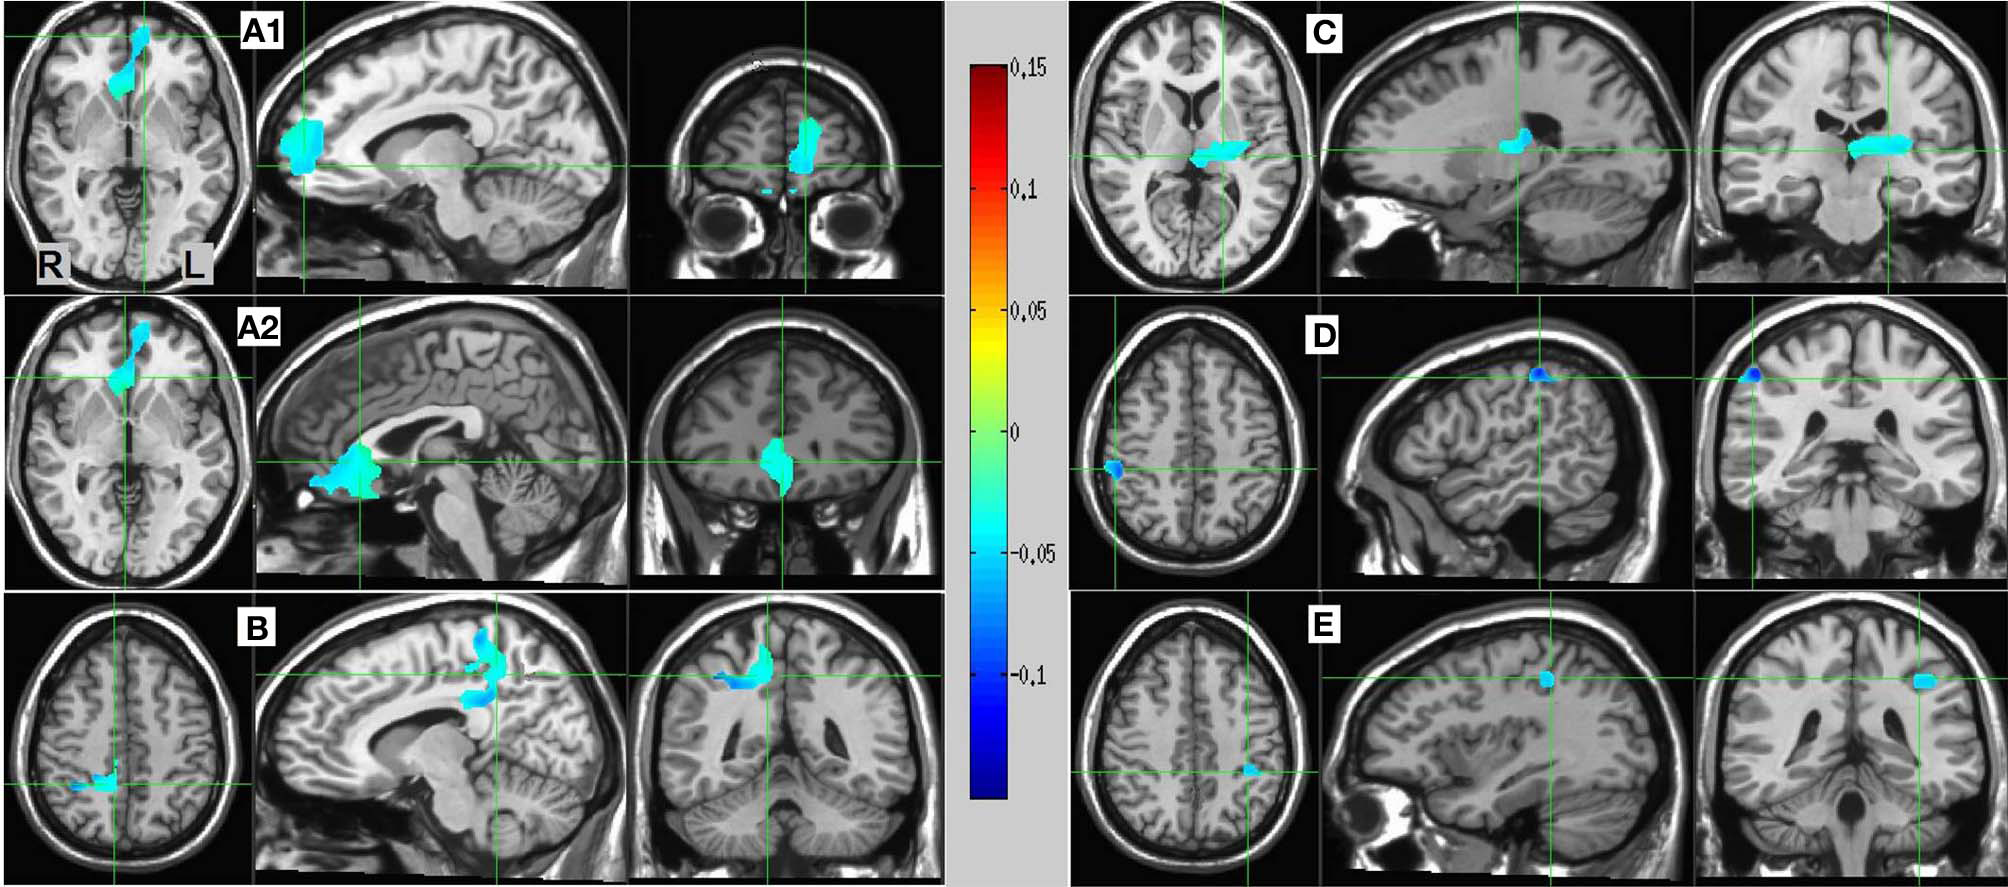

Resulting MS vs. SL 13–25 Hz beta band source estimates were thresholded at t = 3.887, yielding six clusters (for a total of 390 voxels) significant at p < 0.0025 (corrected), all indicating decreased beta power in SL relative to MS (reflecting MS attenuation, see introduction). No significant clusters were found in the high-gamma band range. The largest cluster (182 voxels, mean PSC −0.067, A1 and A2 in Figure 5) consisted of prefrontal and left lateralized regions including the superior frontal gyrus, ventral mPFC, and rostral ACC; bilateral regions including the subgenual ACC, mid orbital, and rectal gyrus; and a region located in the right middle frontal gyrus. The 2nd cluster (109 voxels, mean PSC −0.08, B in Figure 5) was completely in the right hemisphere and included regions from the postcentral gyrus, middle cingulate cortex, paracentral lobule, precuneus, and posterior cingulate cortex (PCC), and the IPL. The 3rd cluster (66 voxels, mean PSC −0.072, C in Figure 5) included large portions of the left thalamus and lentiform nucleus, extending medially to the left posterior insula. The 4th cluster (13 voxels, −0.1 PSC, D in Figure 5) was more anterior and lateral compared to the 2nd cluster, and included regions of the right IPL and postcentral gyrus. The 5th cluster (11 voxels, −0.081 PSC, D in Figure 5) was located in the left IPL, and the 6th cluster (9 voxels, −0.105 PSC, not shown) in the right precentral gyrus and the posterior middle frontal gyrus. See Figure 5 and Table 3 for more details and a visual depiction.

Figure 5

MS vs. SL beamforming source estimates in the beta (13–25 Hz) band. Axial, sagittal, and coronal views (left to right) of group (N = 12) SAM pseudo-F source estimates overlayed on the Colin template. Note that in all images right and left sides are crossed. Color bar indicates PSC degree. Cluster A reveals prefrontal deactivations in two views: the crosshairs in (A1) are on the left anterior medial prefrontal gyrus, and in (A2) on the right subgenual anterior cingulate. Cluster (B) shows deactivation in the posterior medial cortex, with the crosshairs pinpointing the right precuneus. Cluster (C) shows deactivation in the left thalamus; and clusters (D) and (E) deactivations in the right and left inferior parietal lobules, respectively.